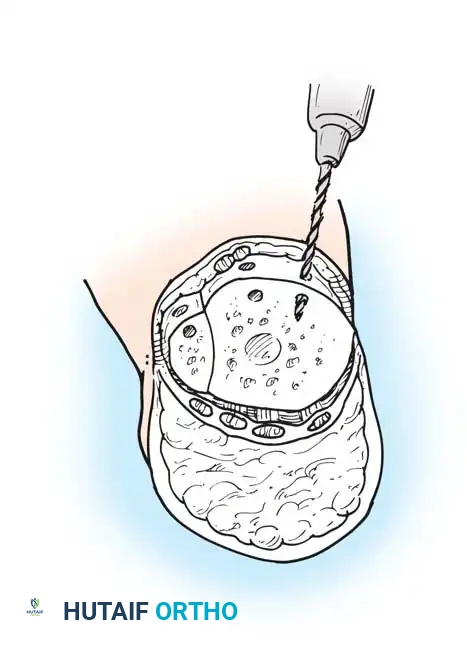

Step 6: Anchoring the Heel Pad (Wagner Technique)

To prevent the disastrous complication of posterior heel pad migration, the pad must be rigidly fixed to the distal tibia.

* Drill several small holes through the anterior edge of the distal tibia and fibula.

- Pass heavy, nonabsorbable sutures through these drill holes and anchor them securely to the robust deep fascia lining the heel flap.